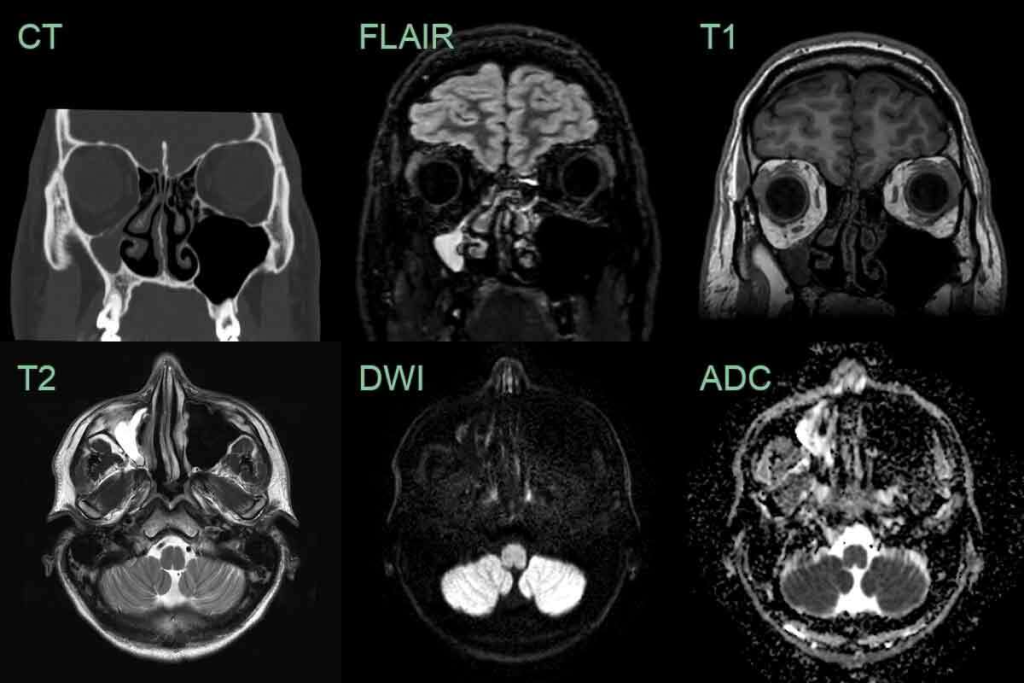

A healthy sinus CT scan shows clear, air-filled sinuses. There are no signs of thickened mucosa or structural problems. This clarity helps us see how healthy sinuses work and drain properly.

Normal sinus imaging shows air-filled cavities. These cavities have a thin mucosa that’s not thick or inflamed. The lack of mucosal thickening is a sign of healthy sinuses.

In a healthy sinus CT scan, the sinus cavities are well-aerated. They are free of fluid or soft tissue opacification. The mucosa is not thickened, showing no inflammation or infection. This is different from sinusitis, where mucosal thickening and fluid buildup are common.

Anatomical variants like nasal septal deviation or Haller cells can block sinus drainage. In a healthy sinus CT scan, these variants are either not present or don’t affect drainage. The absence of such variants ensures proper drainage, lowering the risk of sinusitis.

A healthy sinus CT scan shows good sinus health. Sinusitis can make your mouth taste bad. In serious cases, you might worry about losing your taste. But with the right treatment, you can get rid of these symptoms and feel normal again.

A healthy sinus CT scan shows air-filled spaces without thick mucus. It also doesn’t show any issues that could block drainage. This means your sinuses are clear.

To find out why your mouth tastes bad, see a doctor. They might do a sinus CT scan. This helps figure out what’s causing the problem.